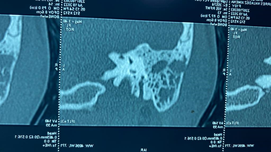

Se realiza tomografía computarizada contrastada de cráneo y cuello; en la cual se observa a nivel de amígdala palatina derecha, una lesión isodensa a tejidos blandos de bordes regulares, que disminuye la luz de la vía aérea y desplaza al espacio parafaríngeo ipsilateral, que no realza al paso del medio de contraste (Figura 2).

|

| (Figura 2) |